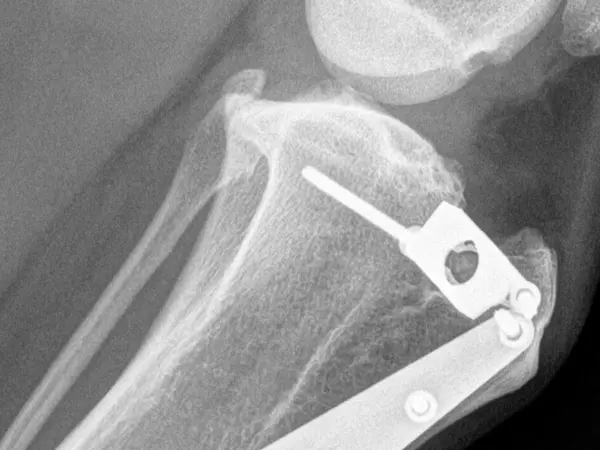

TTA og andre led- og knogleoperationer

Thy Dyrehospital udfører et bredt udvalg af led- og knogleoperationer for at hjælpe både hunde og katte med at genvinde deres mobilitet og livskvalitet.

Vi har stor erfaring med at behandle skader og lidelser, der ofte kræver kirurgisk indgreb, såsom korsbåndsskader, patellaluxation og skader efter fald eller ulykker. Vores team er specialiseret i at håndtere komplekse operationer som TTA (Tibial Tuberosity Advancement) og andre procedurer, der sikrer, at dit kæledyr får den bedst mulige behandling og opheling.